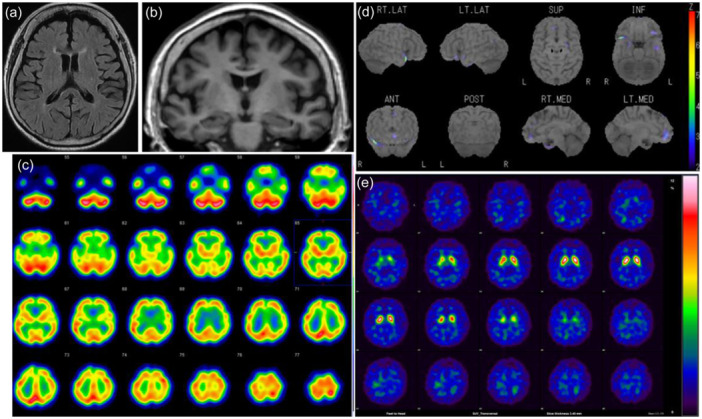

Case presentation: An 87-year-old woman, widowed and living alone, developed psychosis, including paranoia, erotomania, and visual hallucinations, at 84 years old during a period when her interactions with others were limited by the COVID-19 pandemic and osteoarthritis. She was eventually brought to our hospital with a local dementia outreach team. She was admitted and diagnosed with VLOSLP with mild cognitive decline through imaging and neuropsychological tests confirming the absence of dementia. Immediately after admission, her psychotic symptoms became inactive. She was transferred to another psychiatric hospital to prepare for her move to a long-term care facility because her psychosis was alleviated. During admission, she enjoyed the company of others and occupational therapy, and her score on the UCLA Loneliness Scale Version 3 improved from 44 at admission to 35 at discharge.